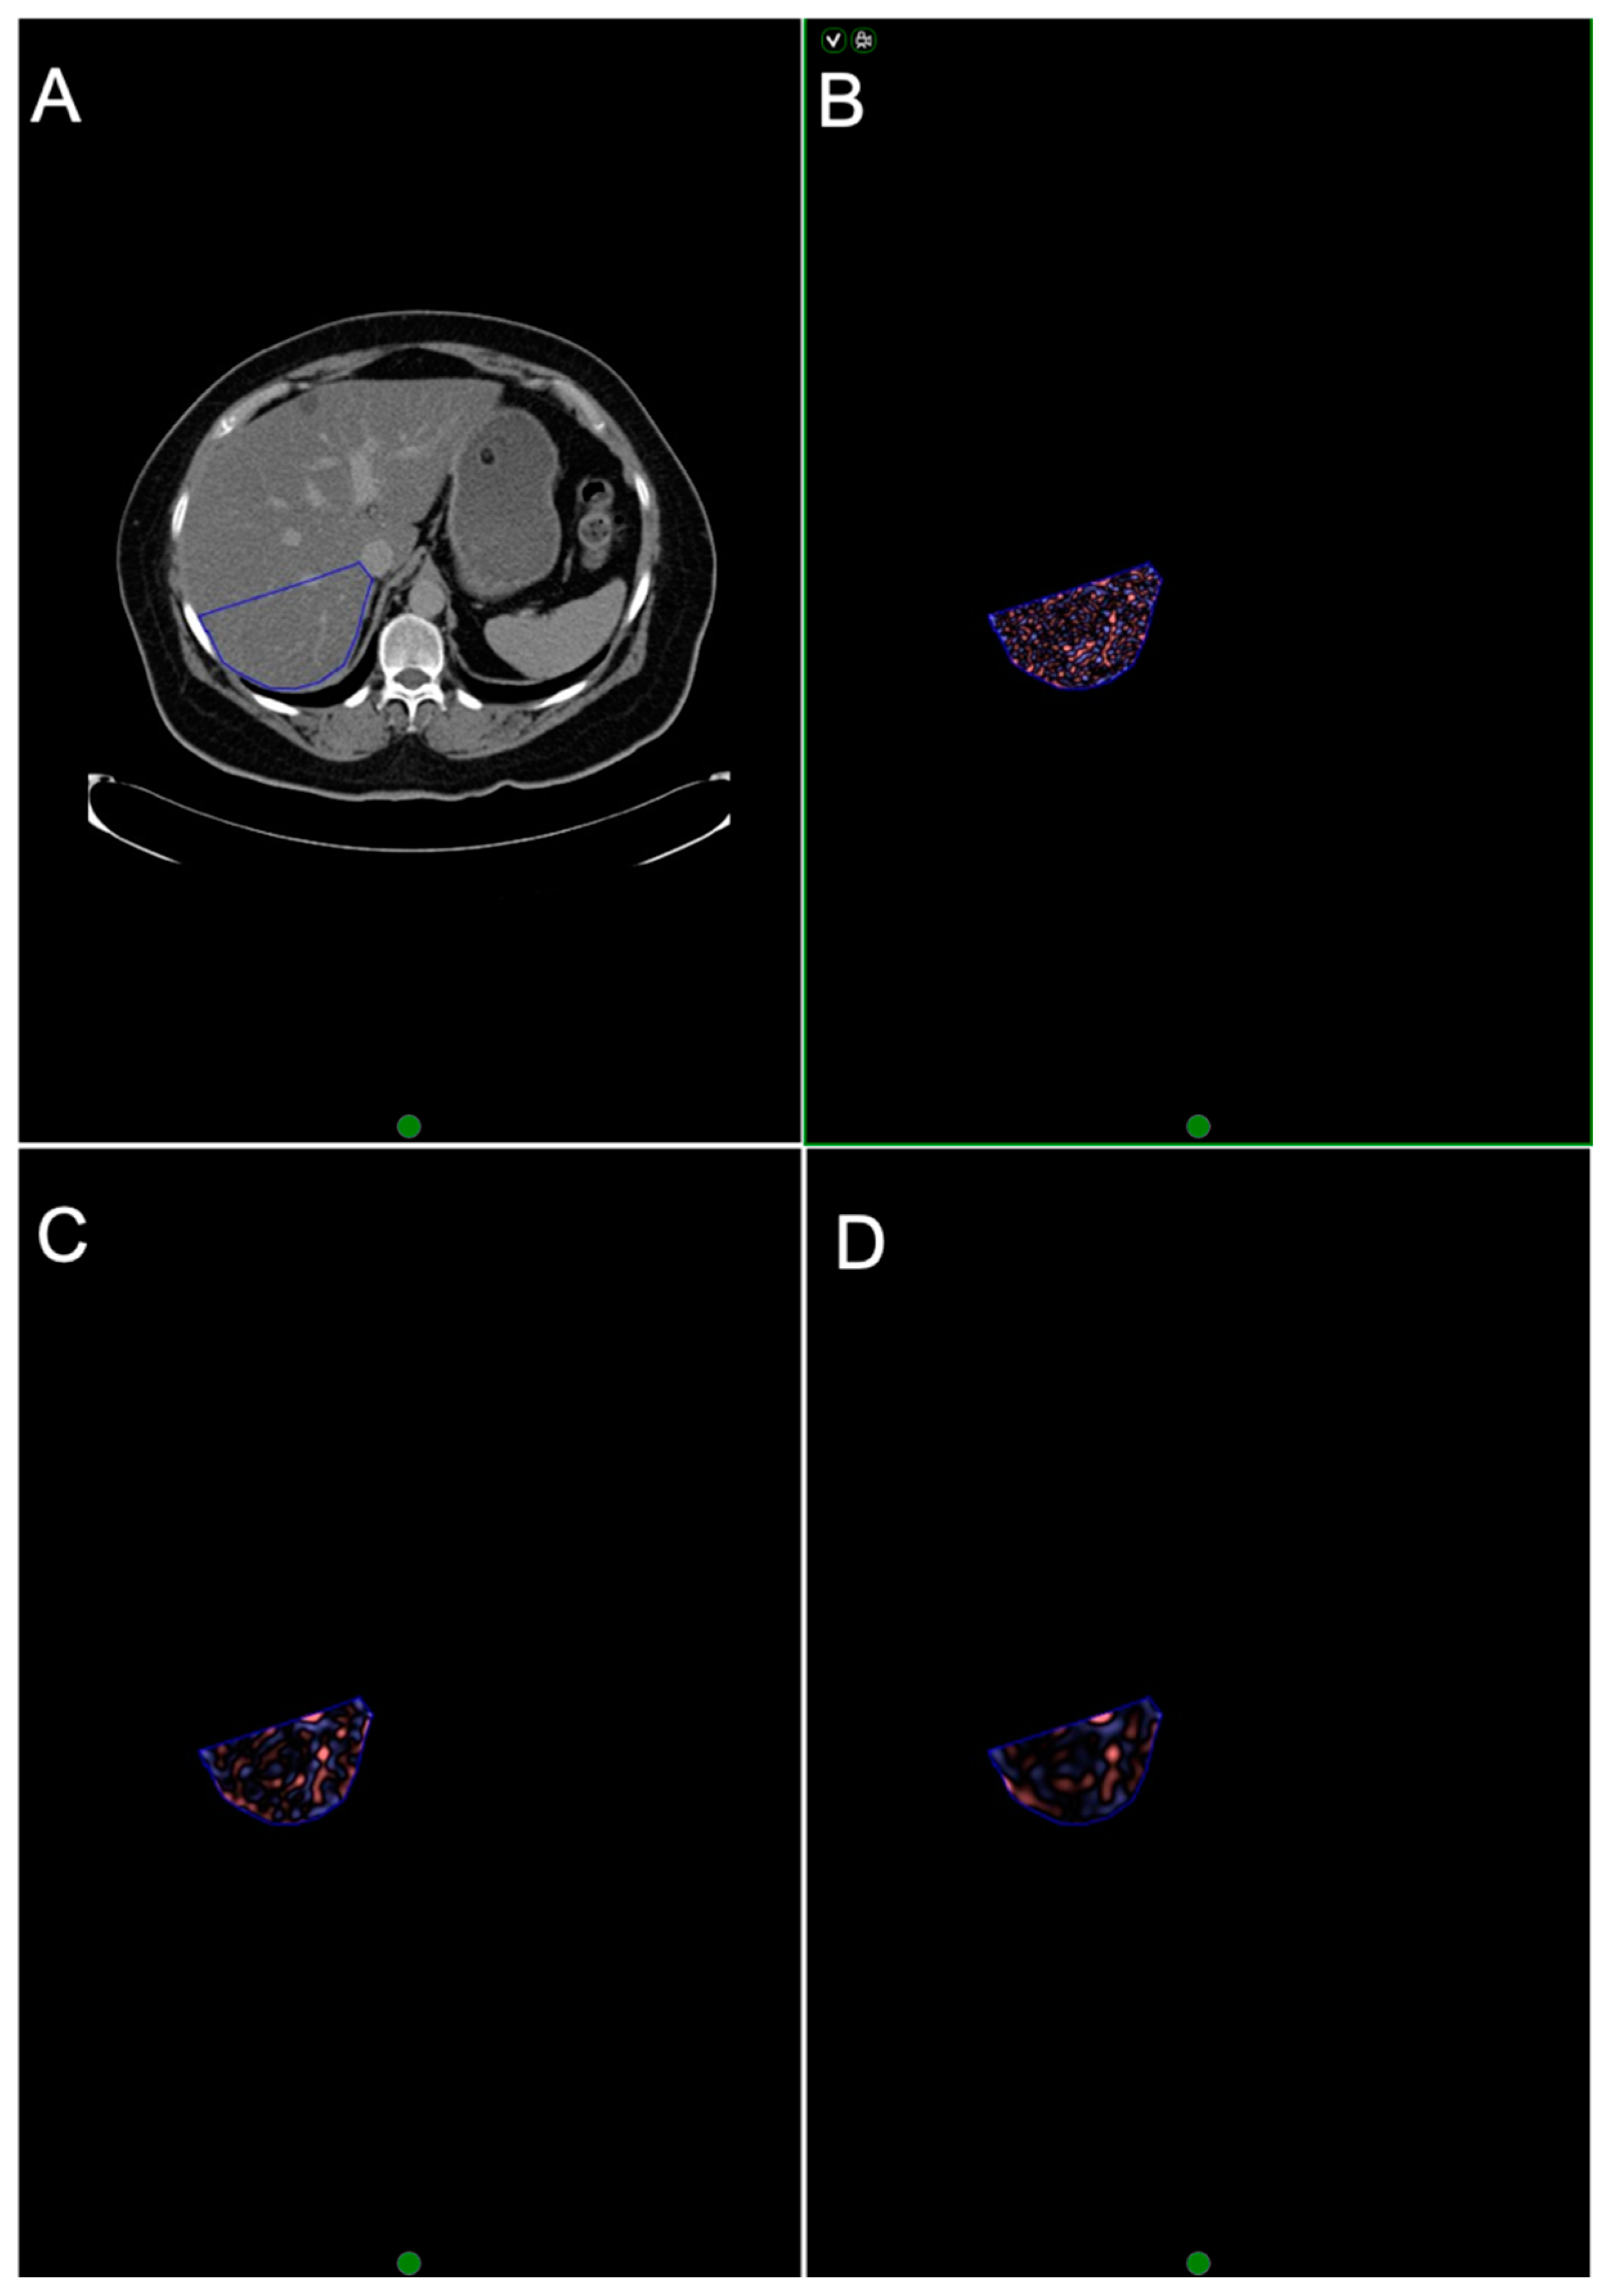

2.4. CTTA